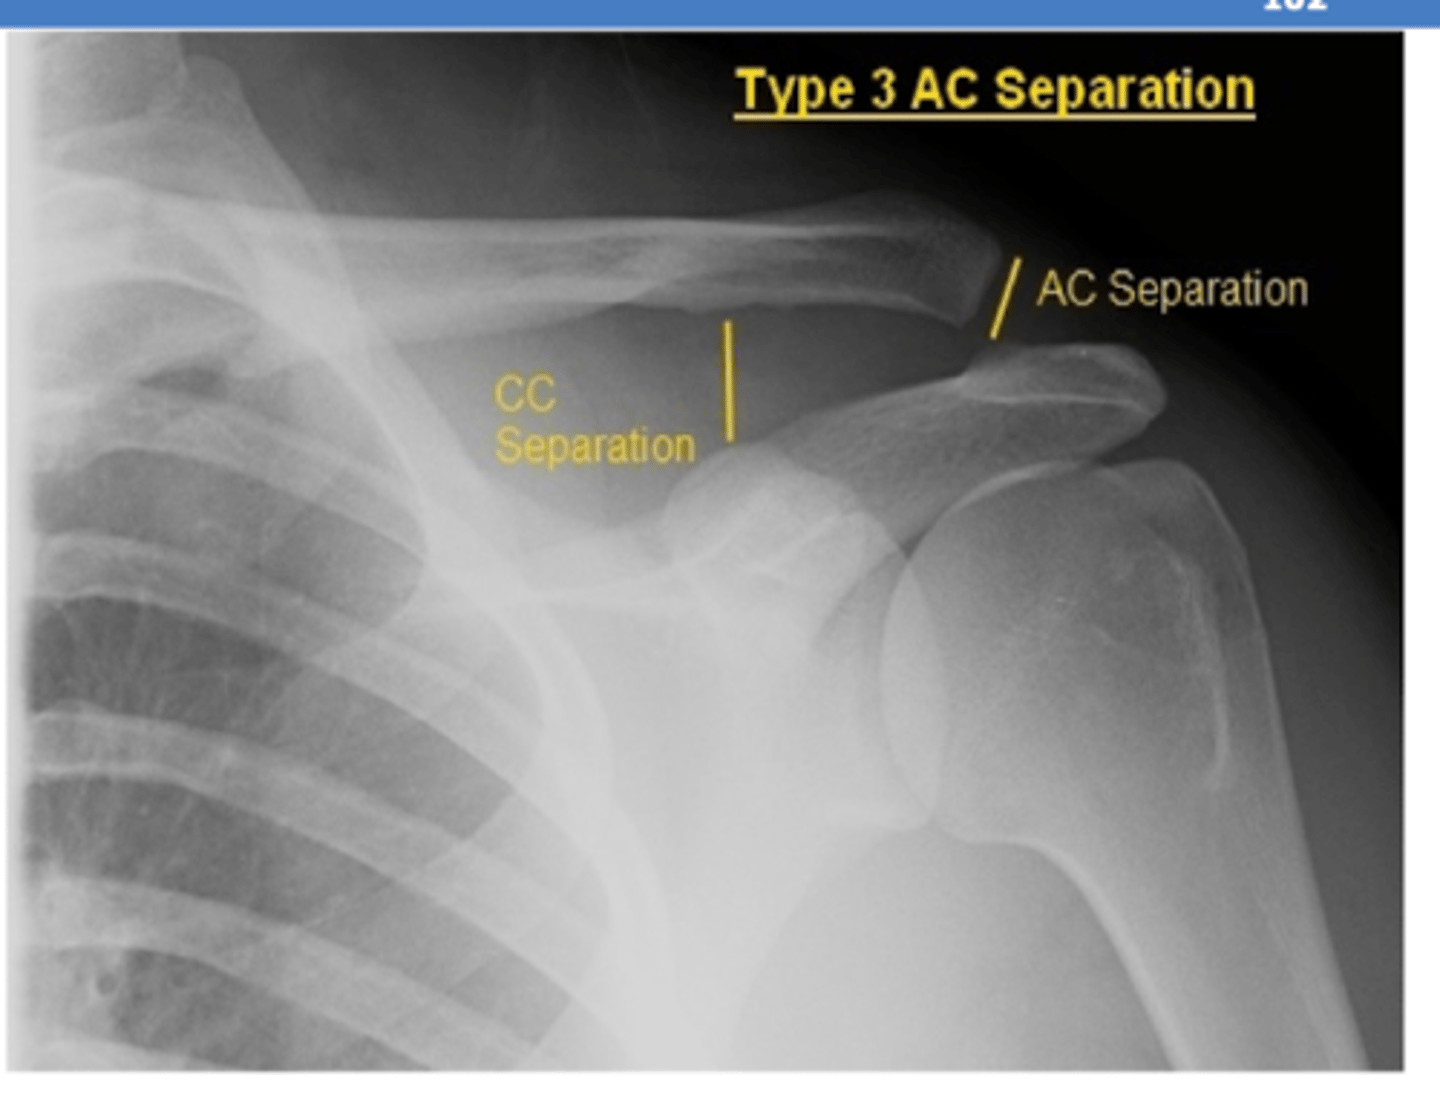

If a patient presents with pain over their AC joint and distal clavicle following fall onto tip of shoulder, what diagnosis is most likely?

AC separation

- will have pain with movement in ALL direction

What are THREE most common types of AC separation?

I → partial disruption of AC ligaments; CC ligaments intact

- no separation

II → AC ligaments are torn; CC ligaments intact

- partial separation of clavicle from acromion

III → AC + CC ligaments are torn

- complete separation

**IV-VI = not common

REVIEW: AC joint separation XR.